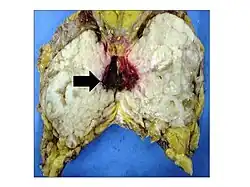

La tumeur phyllode ou cystosarcoma phyllodes est un néoplasme à croissance rapide qui se forme à partir des cellules stromatiques périductales du sein.

La tumeur phyllode est rare et représente moins de 1 % des tumeurs du sein. Elle est généralement bénigne mais éventuellement maligne dans environ 10 % des cas. En raison du caractère récidivant de ce type de tumeur et du risque d'évolution métastasique dans 4 à 17 % des cas, l'enlèvement chirurgical est systématique[1].